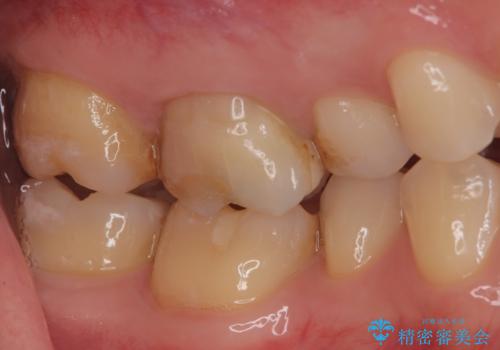

【奥歯のセラミッククラウン】他院で根管治療も必要だといわれた。

- 他院で歯の根っこの先端に膿が溜まっているため治療が必要だといわれた患者様です。

根っこの治療を顕微鏡を見ながら行ってくれる医院を探して当院に来院されました。

以前治療した際のむし歯が大きく、長い年月の間に少しずつ歯髄が死んでしまったと思われる状況でした。

長期にわたる炎症により、口蓋根尖は吸収を起こしていたため、MTAにて充填しています。